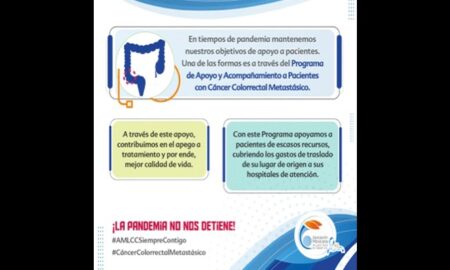

814Salud y nutriciónDiez datos sobresalientes del cáncer colorrectal metastásico

La AMLCC apoya a los pacientes con Cáncer Colorrectal Metastásico con programa de atención integral.